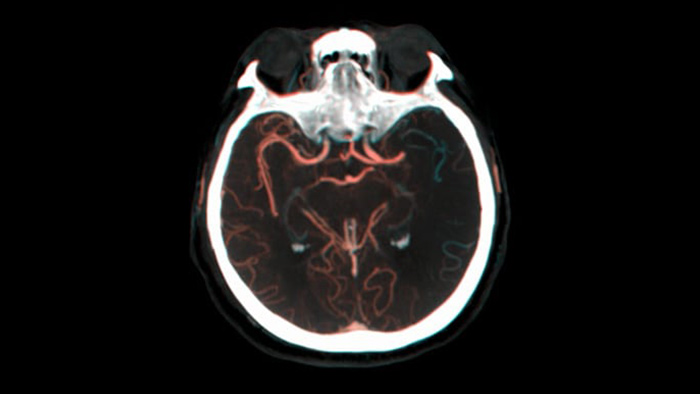

SmartCT Vaso IV

血栓の位置と長さを確認

SmartCT Vasoでは、脳梗塞の梗塞部位の全体像を可視化することができる撮影機能です。SmartCT Vasoは、動脈への造影コーンビームCTに高分解能撮影の技術を組み合わせた撮影技術でrestrictive fillingによる梗塞部位の遠位血管も描出することができ、血栓の位置、長さ、梗塞部位の全体像を視覚化できます。3Dロードマップを組み合わせて使用することにより、術中の血栓回収デバイスのナビゲーションも可能となります。

restrictive fillingによる遠位血管の描出

側副路充満の可視化 image

Dual Viewにより造影コーンビームCT撮影の早期相画像と後期相画像を並べて表示するデュアルビュー機能により、ペナンブラの識別や側副血行路の確認が可能です。